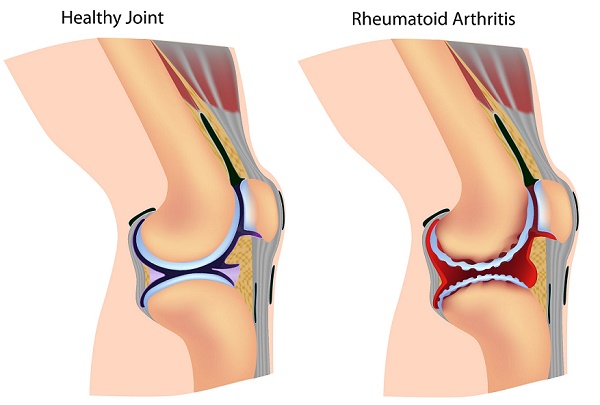

Rheumatoid Arthritis:

Rheumatoid Arthritis is a type of autoimmune arthritis that is caused by a disorder associated with the immune system. The body’s own immune system attacks joints leading to worn out tissues. Rheumatoid arthritis is experienced mostly with small joints; such as knuckles and wrists.

Causes:

Specific triggers of this condition are yet to be determined. However, there are some probable reasons that may lead to a confused state of your immune system, where it generates antibodies to attack joints; thus leading to Rheumatoid arthritis. This condition may also affect other organs of the body and hence referred to as Rheumatoid disease.

- Genetic history of Rheumatoid arthritis

- A virus or bacteria that may interrupt with normal functioning of your immune system

- Some say that excessive smoking may even lead to this condition

- Obesity may make you susceptible to this condition

Symptoms:

- A symmetrical pattern of discomfort. This means pain or stiffness experienced with both wrists, both hips or both feet. This is what differentiates it from other forms of arthritis.

- Extreme fatigue or a continuous feeling of tiredness

- Abrupt weight loss and lack of appetite

- Morning stiffness experienced for several hours for some people

- Fluid accumulation within joints result in swelling

- Joints become sensitive and tender

- Your joints appear red and warm

- Shortness of breadth when condition affects lungs

- Chest pain and breathing trouble when heart is affected

- Hoarseness in rare cases